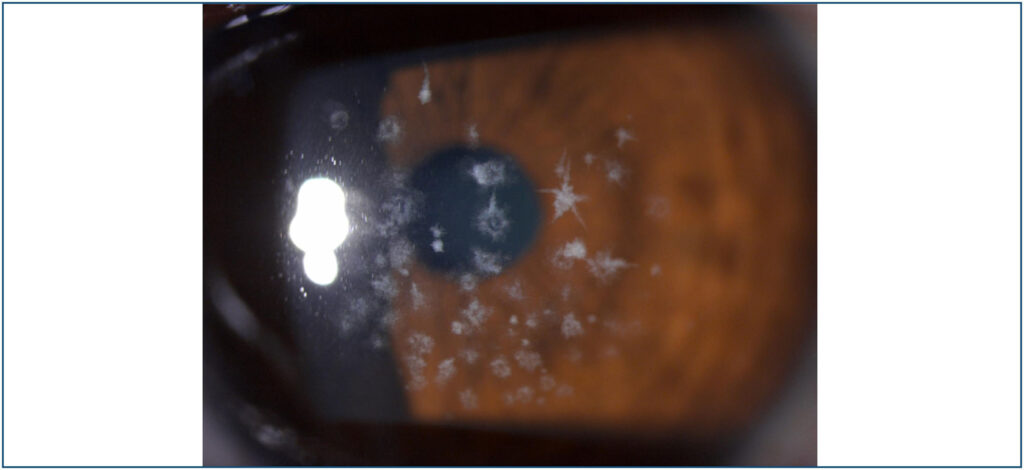

Avellino corneal dystrophy: corneal stars

A 32-year-old woman presented for routine ophthalmic examination. The patient has myopia of −6.25 in both eyes with best corrected visual acuity at 8/10 bilaterally. On slit-lamp examination, she was found to have crumb-like and star opacities, grey-white deposits in the anterior corrneal stroma (-). Clear areas were present between the opacities. The peripheral cornea was clear. Her best corrected visual acuity was 8/10 bilaterally. A diagnosis of granular dystrophy type II was made.